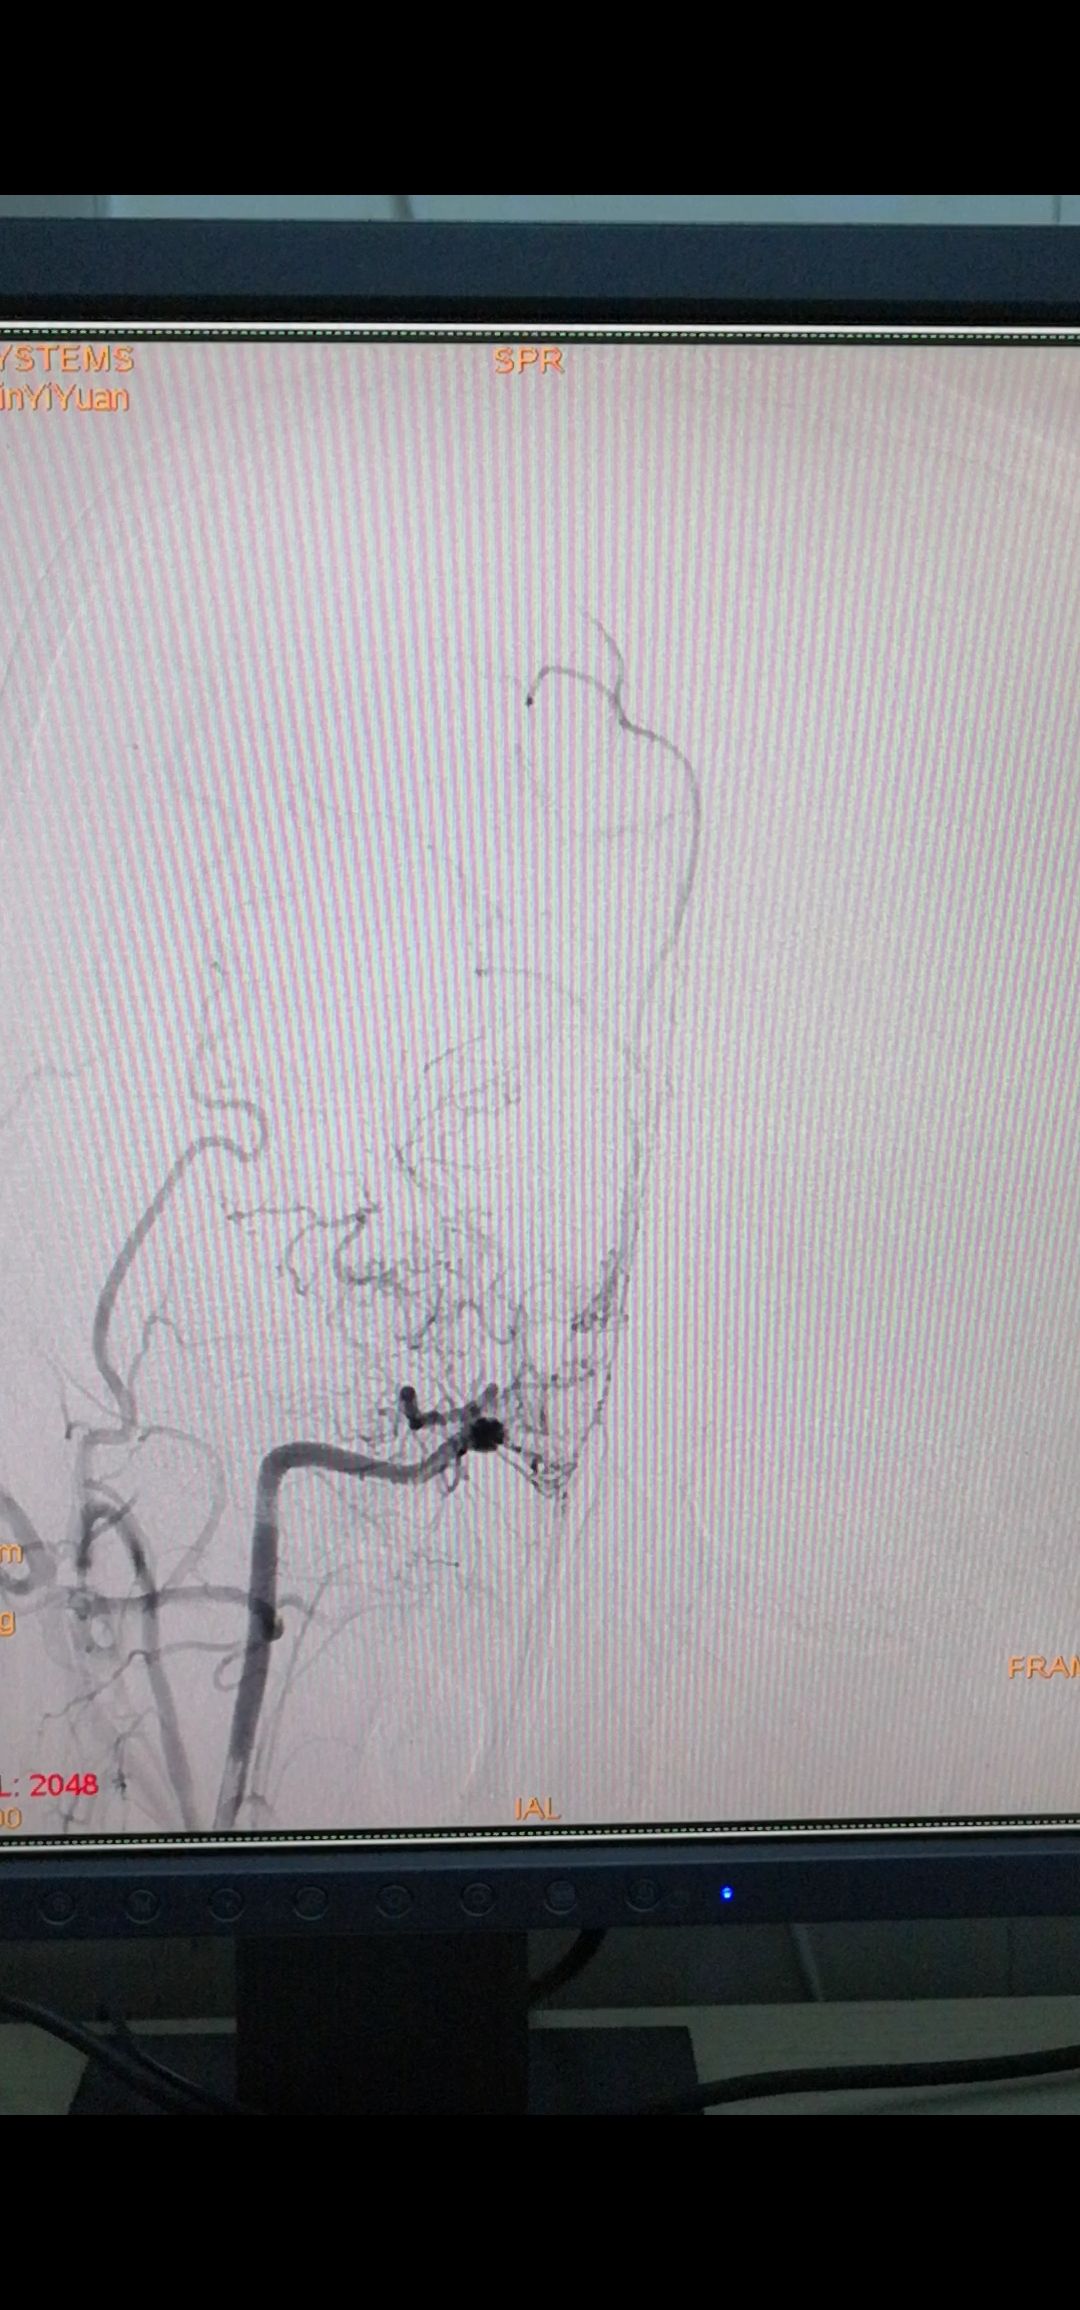

颈外动脉